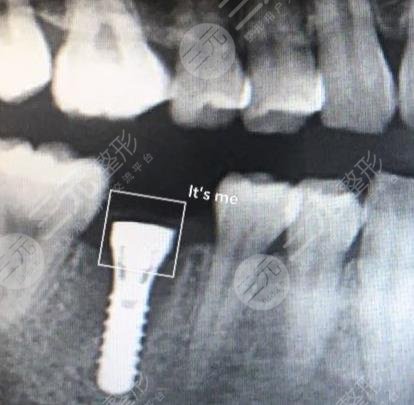

三、上海牙防所种植牙手术案例分享

手术之前:我是一个很爱美的人,可是却因为牙齿磕掉了一颗,所以显得特别的不好看,而且还是在前门牙的部位,这种情况让我感到特别的自卑,有的时候不知道该用什么方法去解决,就在较近几年很多人都在说,现在医院里边特别流行有一种叫种植牙手术的,不知道管不管用,我想去医院尝试一下,那天来到医院和这里的整形专家沟通了一下,把我想知道的都问了一下医生,医生也中和我的实际情况为我设计了手术的方法,整个手术在缓解的过程中大概只用了三个小时。

手术当中:在手术完成之后,医生让我在医院多呆几个小时观察一下是不是有什么不良的情况,在医院观察了几个小时之后,并没有发生任何的不良情况,我就回家了,回家之后我和医生一直保持着沟通,有什么不懂的都会及时的问医生,医生也会告知我,就这样手术大概过了有8个月左右的时间我的牙齿就恢复了,现在的牙齿和天生的根本看不出什么区别来,而且特别的坚固,在这期间牙齿也没有出现松动,吃什么东西都不妨碍,我真的是好开心很感谢这家医院的医生。